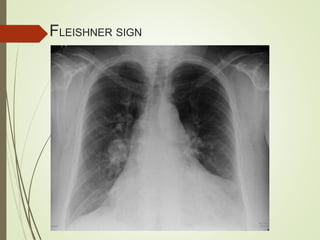

CHEST X-RAY

Fleishner sign